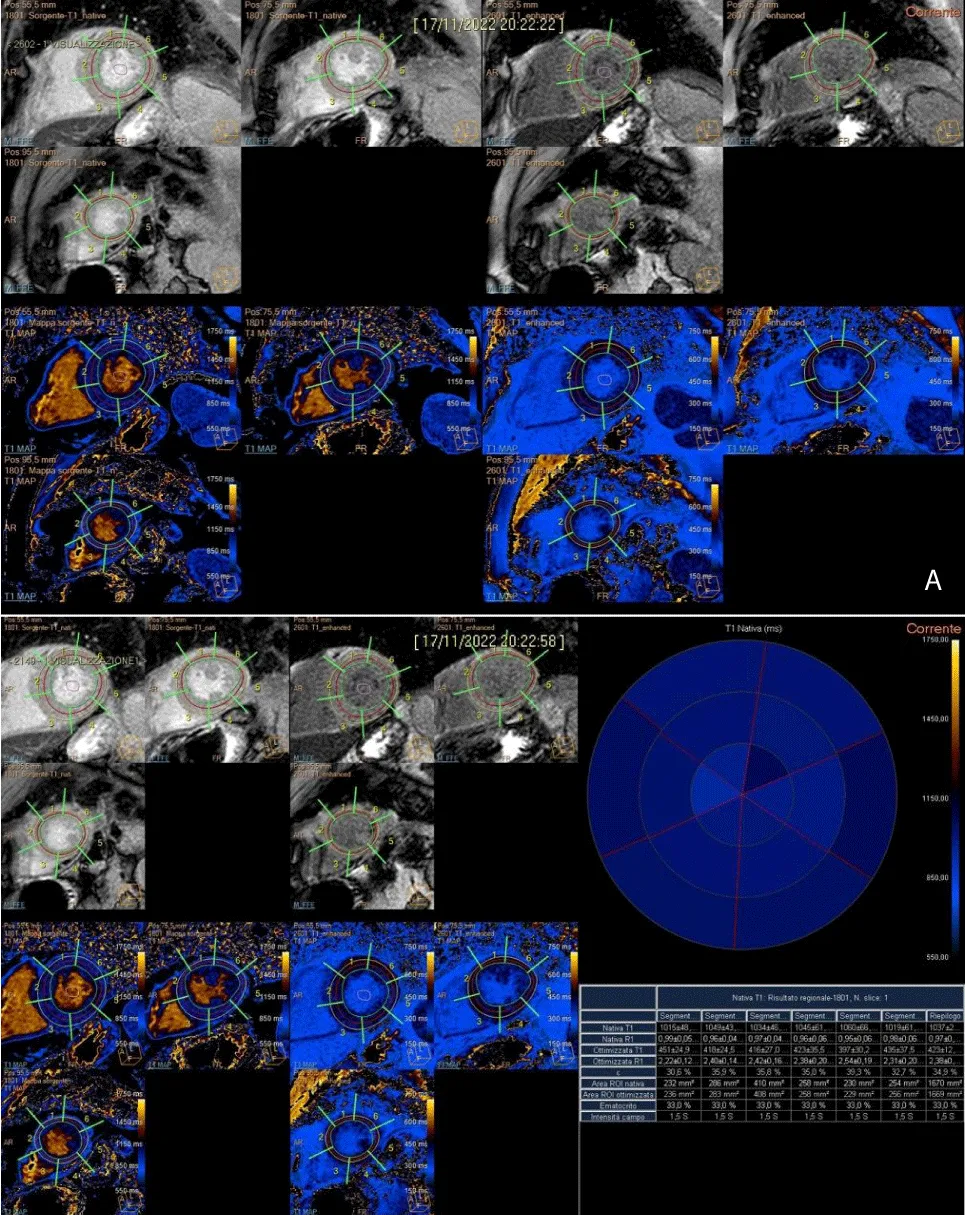

For the measurement of T1 and T2 relaxation times, a global approach is used, including the complete apical, midventricular, and basal SAX (short axis). Endocardial and epicardial contours of the LV are traced in all sequences, excluding fat, pericardium, and blood from analysis; an isolated ROI (region of interest) is inserted in the center of the blood in T1 mapping sequences (native and enhanced).

In the subsequent segmentation and results phases, the value by segment and average value for a section are extrapolated along 3 main plans acquired. In the re-elaboration of T1 in the segmentation phase, the hematocrit values are extrapolated from the laboratory parameters of the sampling carried out on the morning of the day of the survey. The addition of the hematocrit values is essential to extrapolate the ECV values, evaluated as both segment value and average value by section (Figure 4A and 4B).

Download Image

Figure 4: A). Post-processing T1 mapping, with the tracing of sub-endocardial and sub-epicardial borders, along three short-axial planes (basal, middle, and apical) and demarcation of intraluminal ROI. B). Semi-automatic quantitative analysis of T1 native, T1 enhanced with extrapolation of ECV.